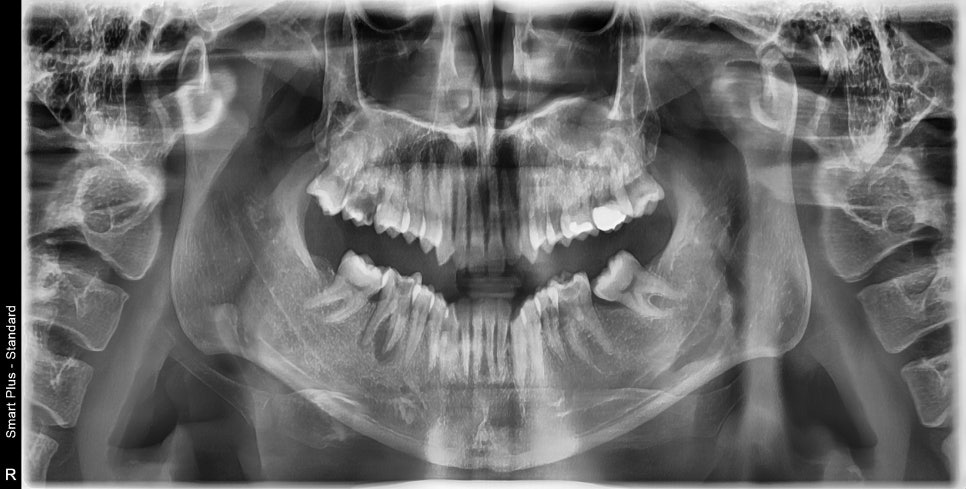

이 환자분도 충치에 의해서 치아를 잃어버리셨고

교정도 원하고 계셔서

우선은 교정을 먼저 하고 교정을 진행하다가 치아가 없는 공간에 임플란트를 해 넣기로 하였습니다.